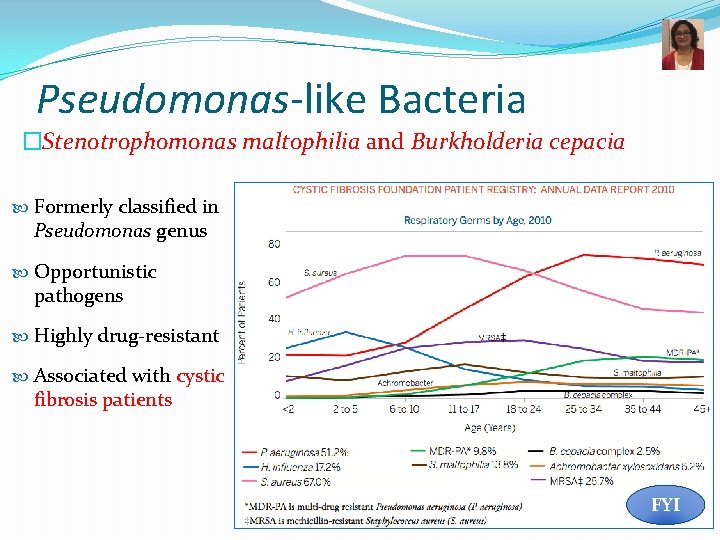

Pseudomonas-like Bacteria �Stenotrophomonas maltophilia and Burkholderia cepacia Formerly classified in Pseudomonas genus Opportunistic pathogens Highly drug-resistant Associated with cystic fibrosis patients FYI 36